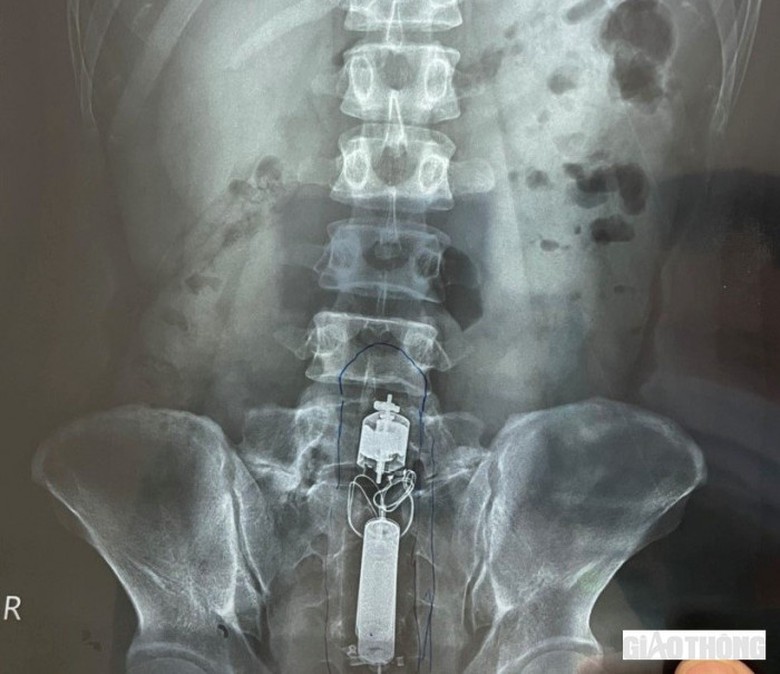

Ảnh X-quang nhìn thấy rõ dị vật trong trực tràng.

Qua hình ảnh chụp X-quang, các bác sĩ phát hiện dị vật nằm sâu bên trong trực tràng. Theo kết quả test nhanh, bệnh nhân dương tính với HIV.

May mắn là dị vật trơn, không có góc cạnh nên các bác sĩ có thể nội soi lấy dị vật nhanh chóng. Dị vật lấy ra là một dương vật giả, có chiều dài 20 cm.